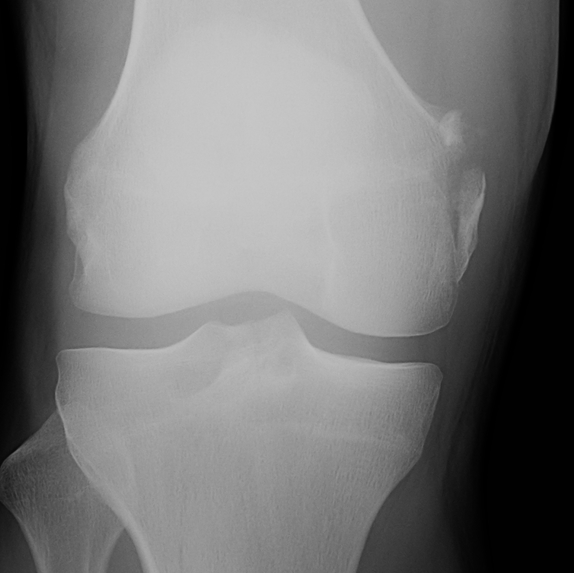

X-ray

Usually normal in acute injury

Bony avulsions (rare)

Bony avulsion of MCL on femoral side

Pellegrini-Stieda Lesion

- calcification at insertion of femoral MCL

- indicative of chronic injury

Acute femoral avulsion